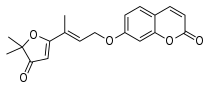

Species-dependent divergences may hamper the extrapolation of inhibitor potencies.[33]

Reversible

Natural

Synthetic

- Safinamide and analogs[38]

- 5H-Indeno[1,2-c]pyridazin-5-ones[33][39][40] (see 3d model)

- Substituted chalcones[41]

- 2-(N-Methyl-N-benzylaminomethyl)-1H-pyrrole[42]

- 1-(4-Arylthiazol-2-yl)-2-(3-methylcyclohexylidene)hydrazine[43]

- 2-Thiazolylhydrazone[44]

- 3,5-Diaryl pyrazole[45]

- Pyrazoline derivatives[46][47]

- Several coumarin derivatives[48] and #C19*[33] (see 3d model)

- Phenylcoumarins, extremely subtype selective[49] and further analogs[50][51][52] (see 3d model)

- Chromone-3-phenylcarboxamides[53]

- Isatins[54]

- Phthalimides[55]

- 8-Benzyloxycaffeines[56][57] and CSC analogs[58]

- (E,E)-8-(4-phenylbutadien-1-yl)caffeines,[59] with A2A antagonistic component

- Indazole- and Indole-5-carboxamides[60]